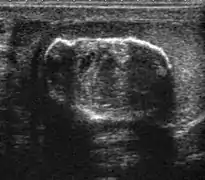

![]() Sonography of a normal testis. The normal testis presents as a structure having homogeneous, medium level, granular echotexture. The mediastinum testis appears as the

hyperechoic region located at the periphery of the testis as seen in this figure. | |

The normal adult testis is an ovoid structure measuring 3 cm in anterior-posterior dimension, 2–4 cm in width, and 3–5 cm in length. The weight of each testis normally ranges from 12.5 to 19 g. Both the sizes and weights of the testes normally decrease with age. At ultrasound, the normal testis has a homogeneous, medium-level, granular echotexture. The testicle is surrounded by a dense white fibrous capsule, the tunica albuginea, which is often not visualized in the absence of intrascrotal fluid. However, the tunica is often seen as an echogenic structure where it invaginates into the testis to form the mediastinum testis. In the testis, the seminiferous tubules converge to form the rete testes, which is located in the mediastinum testis. The rete testis connects to the epididymal head via the efferent ductules. The epididymis is located posterolateral to the testis and measures 6–7 cm in length. At sonography, the epididymis is normally iso- or slightly hyperechoic to the normal testis and its echo texture may be coarser. The head is the largest and most easily identified portion of the epididymis. It is located superolateral to the upper pole of the testicle and is often seen on paramedian views of the testis. The normal epididymal body and tail are smaller and more variable in position.